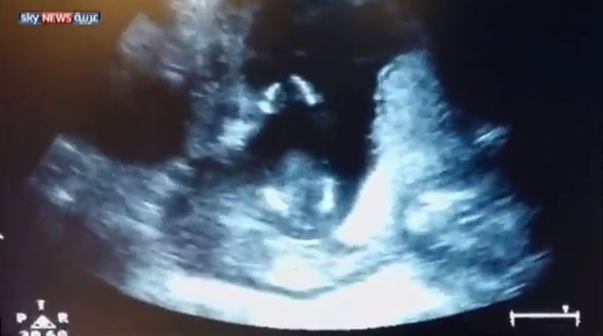

حصد فيديو لجنين يصفق داخل رحم أمه أكثر من مليوني مشاهدة على موقع يوتيوب.

وأثار الفيديو ضجة على مواقع التواصل الاجتماعي، إذ ظهر الجنين يصفق على أنغام الأغنية الإنجليزية “إذا كنت سعيدا صفق بيديك”، والتي كان والده يغنيها في إحدى جلسات التصوير بالأمواج فوق الصوتية.

ونقلت صحيفة مترو البريطانية، عن جين كاردينال والدة الطفل، قولها “إن الفيديو حقيقي، وإن طفلها صفق بالفعل، ولكن ليس على أنغام الأغنية”.

وأضافت كاردينال “قام الطبيب بإعادة شريط التسجيل، وبدأ والده في الغناء بشكل متزامن مع تصفيقه، لنحصل على هذا الفيديو المدهش”.